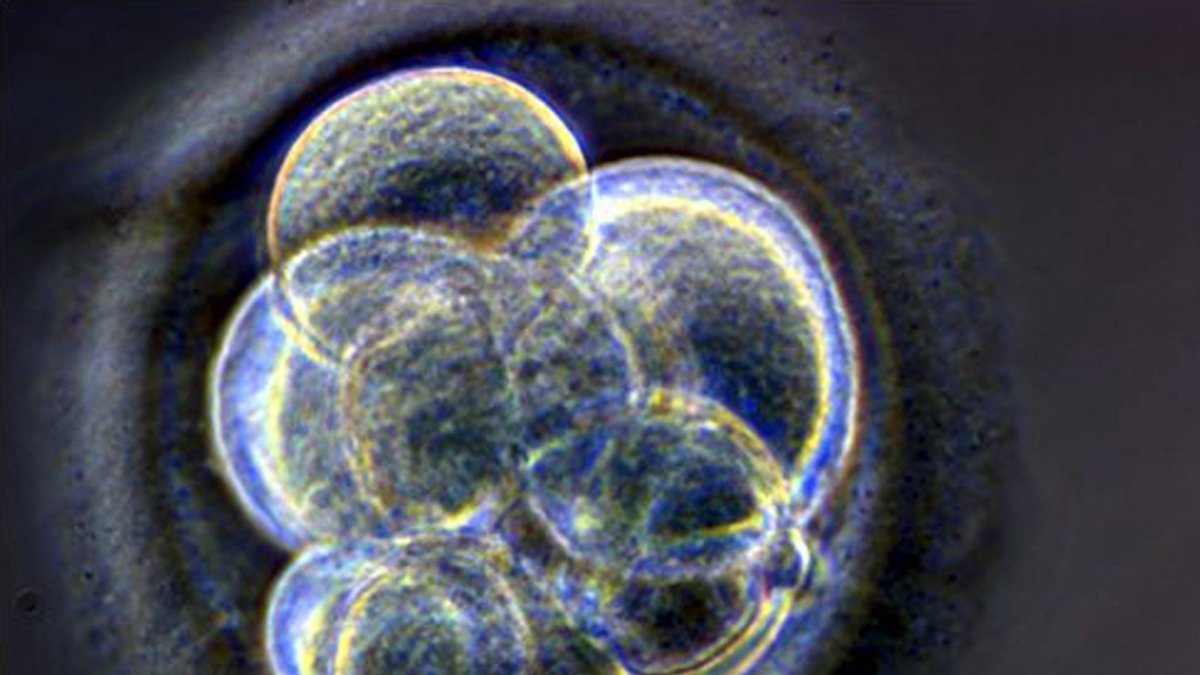

Archivo. Embrión humano clonado de tres día